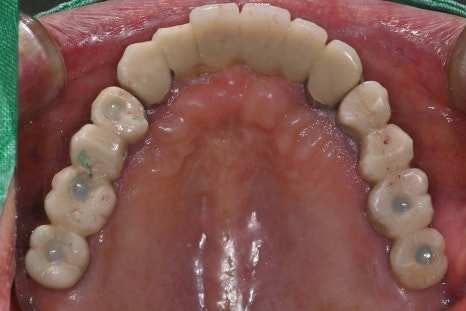

Left photo: Most of the upper teeth had implant prostheses, but the screw access holes were open and needed repair.

Left photo: The upper prosthesis had good overall fixation and the bite was designed to be stable.

Left photo: Front view of the completed prosthesis. Both esthetics and function were restored satisfactorily.